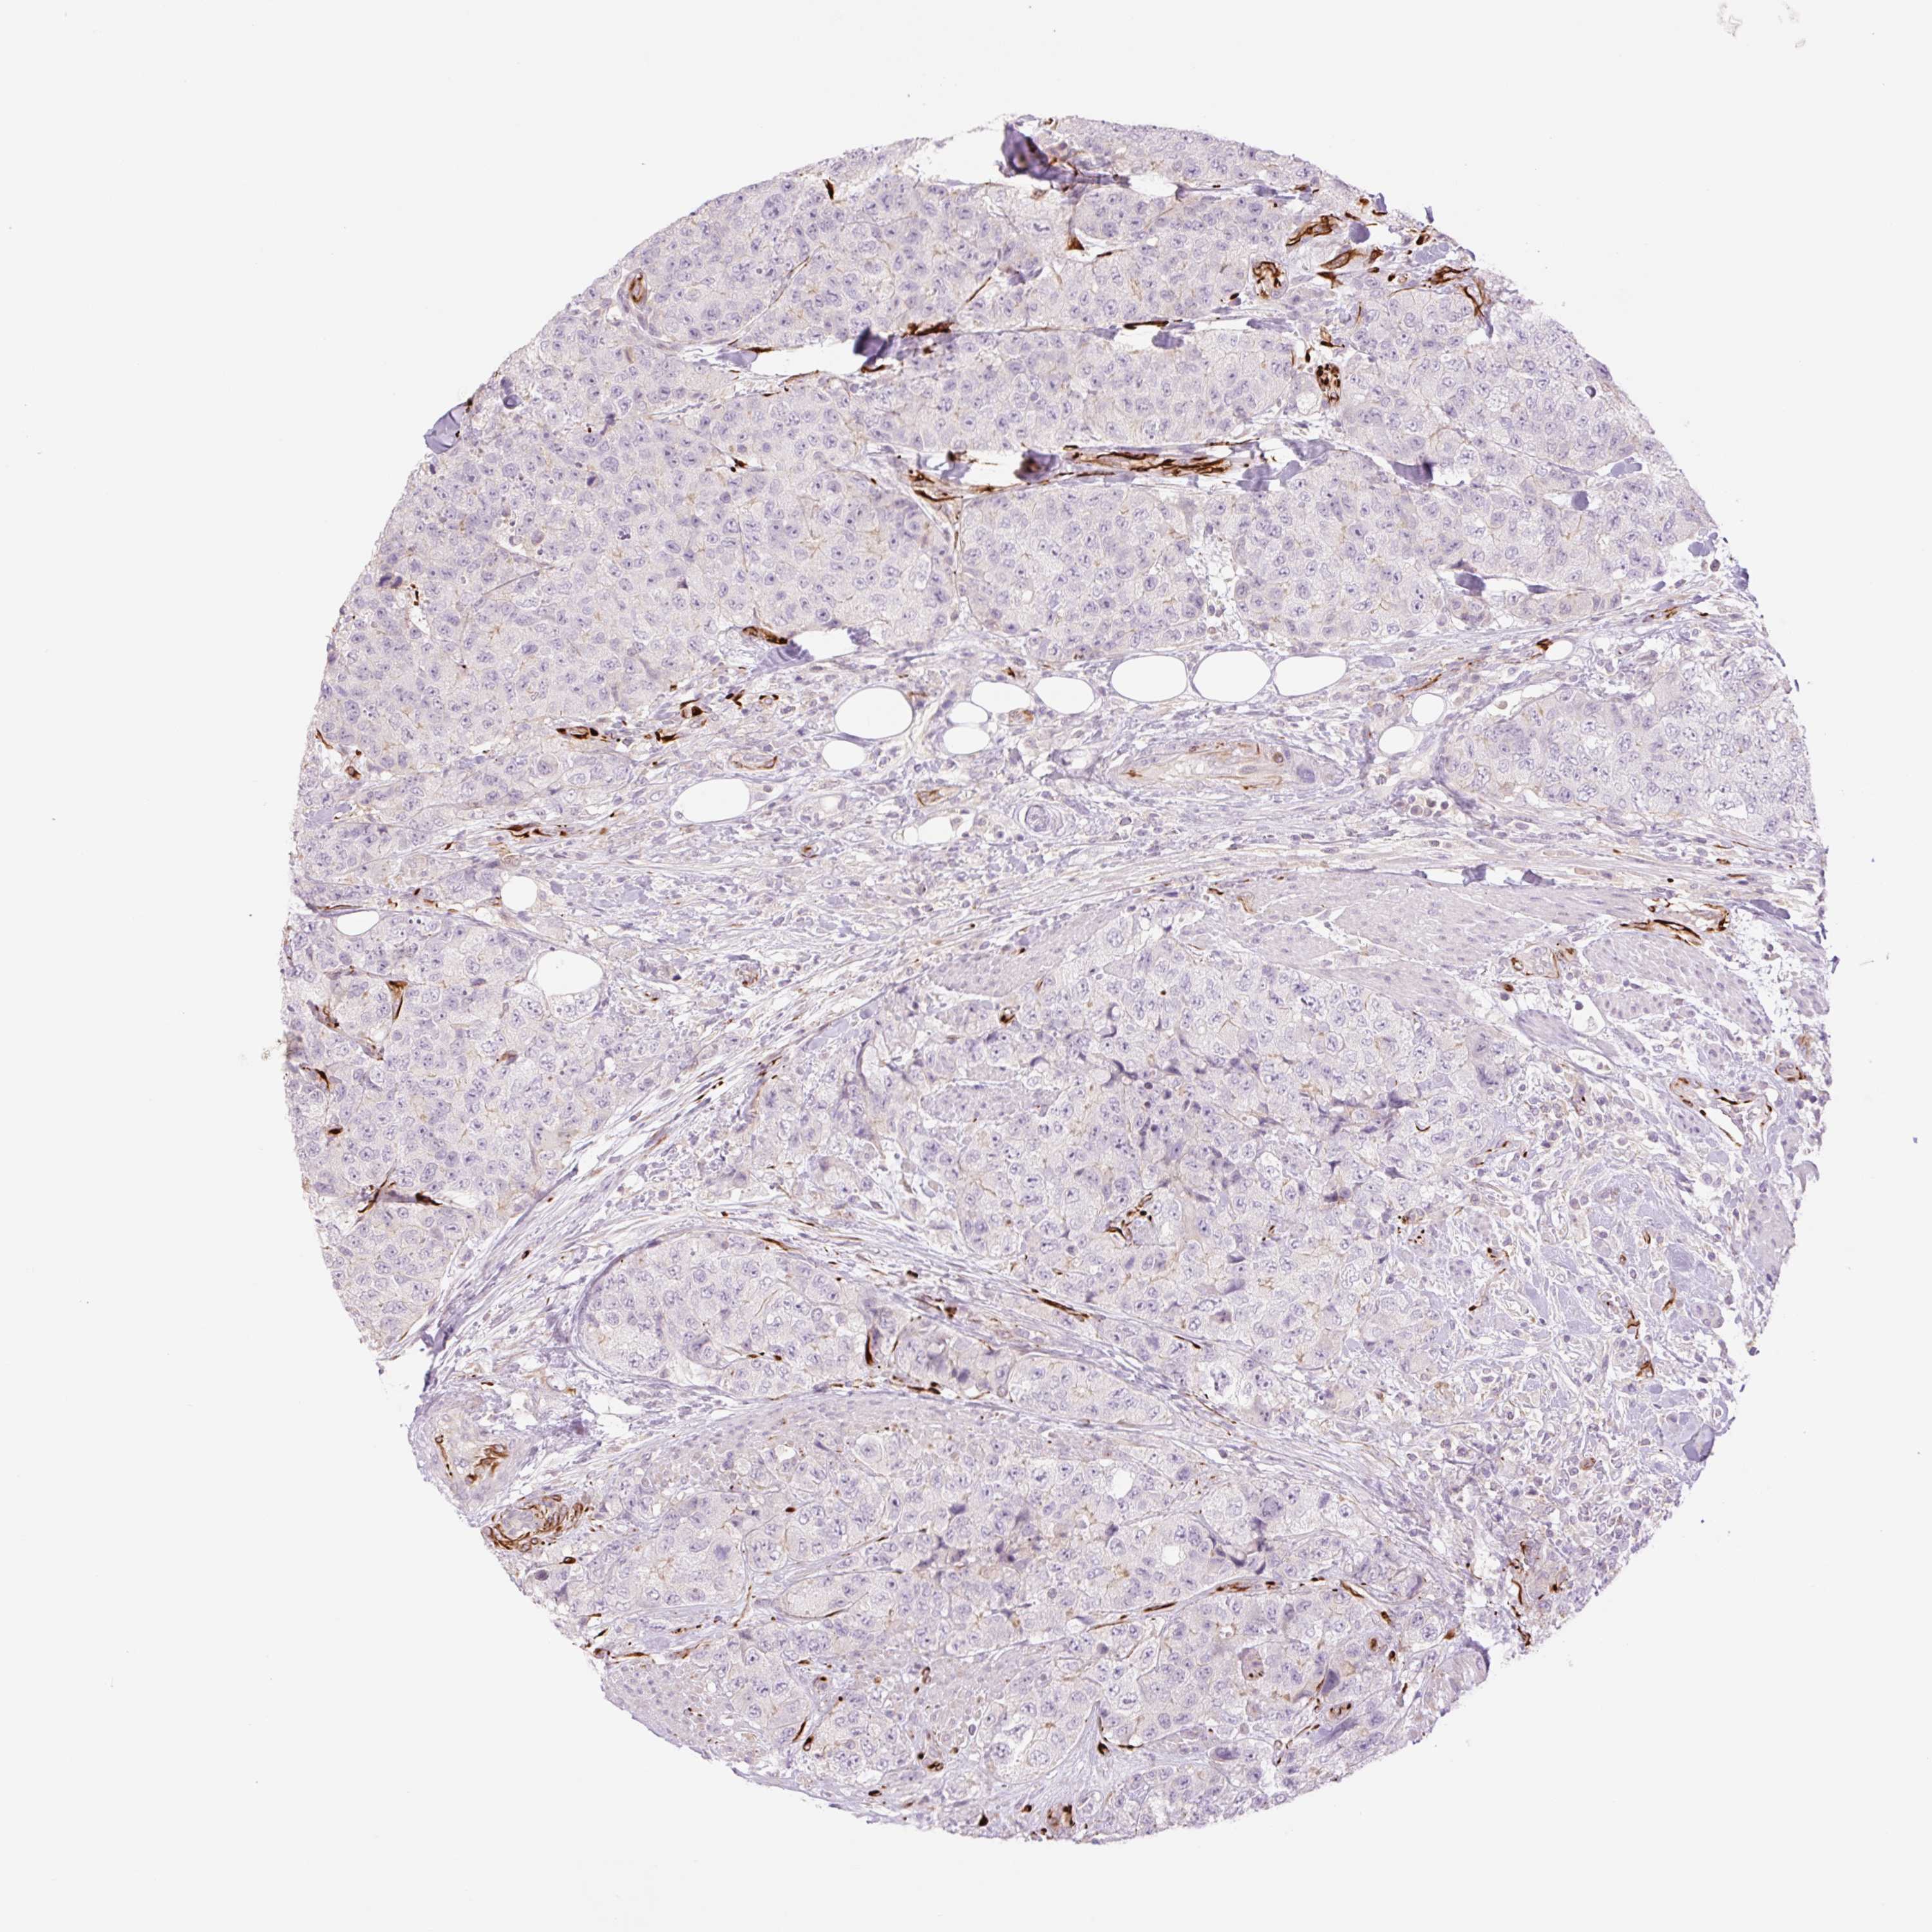

UROTHELIAL CANCER - Protein expressioni

A mouse-over function shows sample information and annotation data. Click on an image to view it in a full screen mode. Samples can be filtered based on level of antibody staining by selecting one or several of the following categories: high, medium, low and not detected. The assay and annotation is described here.

Note that samples used for immunohistochemistry by the Human Protein Atlas do not correspond to samples in the TCGA dataset.

Antibody stainingi

Antibody staining in the annotated cell types in the current human tissue is reported as not detected, low, medium, or high, based on conventional immunohistochemistry profiling in selected tissues. This score is based on the combination of the staining intensity and fraction of stained cells.

Each image is clickable and will lead to virtual microscopy that enables deeper exploration of all samples and also displays staining intensity scores, fraction scores and subcellular localization as well as patient and tissue information for each sample.

Antibody HPA055721

Staining

High

Medium

Low

Not detected

Intensity

Strong

Moderate

Weak

Negative

Quantity

>75%

75%-25%

<25%

None

Location

Urothelial carcinoma, High grade

Urothelial carcinoma, NOS

Urothelial carcinoma, Low grade